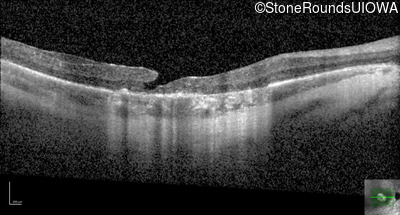

Optical Coherence Tomography - Left - 20/32 +2

Exemplar / OCT Stack